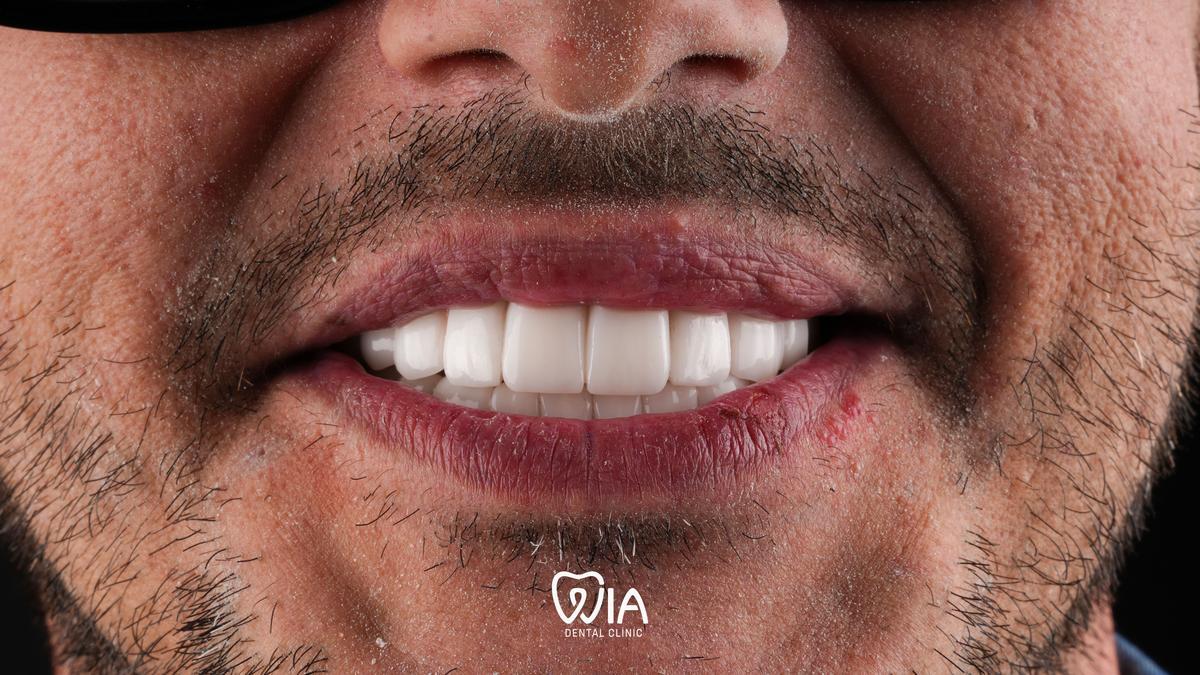

Real stories from real people

Hollywood Smile

Real results of our patients